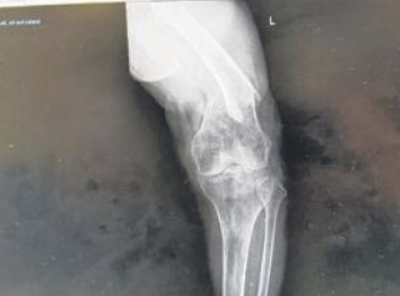

Nào ngờ cuối tháng 10 vừa qua, người đàn ông này bỗng phát hiện bên chân trái của mẹ bị sưng một cách bất thường, khi đi bệnh viện chụp X quang thì kết quả cho thấy là bà bị rạn xương.

Muốn biết chuyện gì đã xảy ra với mẹ mình, Xue đã xem lại camera gắn ở phòng của mẹ mới biết nguyên nhân gây ra vết thương trên cơ thể người phụ nữ đã xảy ra vào ngày 19/10 vừa qua.

Hóa ra Kyi - người được nhận lương để chăm sóc cho mẹ của anh, lẽ ra phải là người giúp đỡ và bảo vệ bà cụ, thì đã nhẫn tâm đấm vào mặt nạn nhân tới 4 lần, khiến nạn nhân bị ngã và rạn xương đùi.

Đoạn băng hình do camera ghi lại cho thấy, Kyi đã để mẹ của Xue ngồi ở mép giường để giúp bà đứng lên và tập luyện. Sau khi bà cụ đã loạng choạng rồi ngã xuống sàn nhà, Kyi đã lôi người phụ nữ đáng thương ngồi lên giường rồi dùng tay đấm vào mặt nạn nhân 4 lần, khiến bà bị ngã và rạn xương đùi.